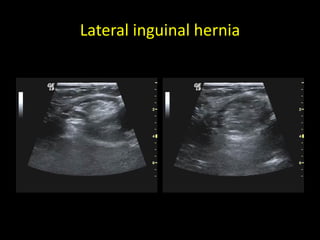

Lateral inguinal hernia

Indirect Hernia (Lateral Hernia)